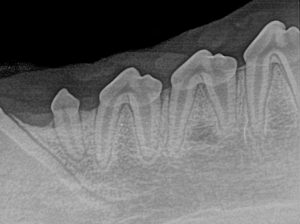

Canine Full Mouth Radiograph Example